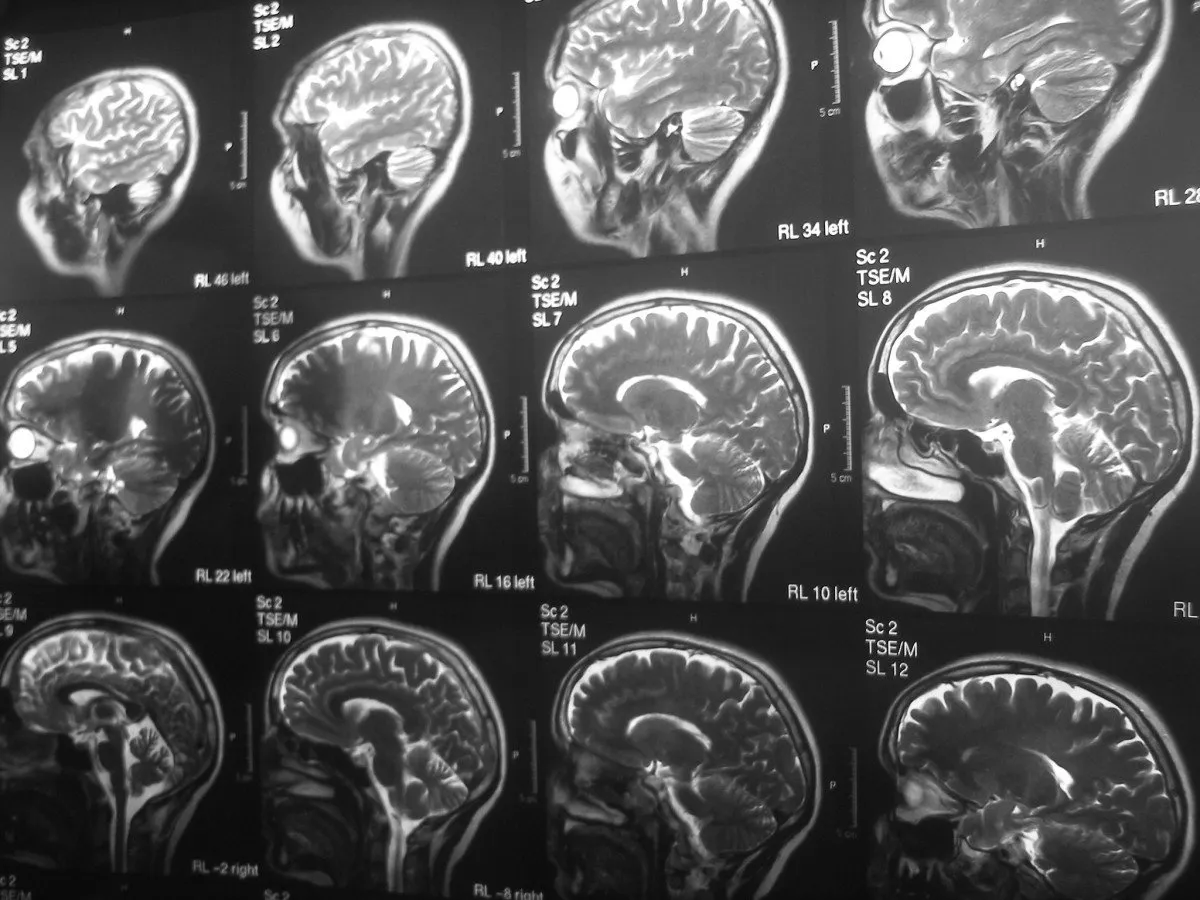

Grzyby halucynogenne, a w szczególności zawarta w nich psylocybina, wywołują głębokie i złożone zmiany w funkcjonowaniu mózgu, które manifestują się jako znaczące transformacje w percepcji, myśleniu i świadomości. Zrozumienie tych mechanizmów pozwala na obiektywną ocenę ich wpływu na ludzki umysł.

Psylocyna posiada strukturę chemiczną niezwykle podobną do serotoniny, jednego z najważniejszych neuroprzekaźników w ludzkim mózgu, który odpowiada za regulację nastroju, snu, apetytu i wielu innych funkcji. Ta podobieństwo pozwala psylocynie na wiązanie się z receptorami serotoninowymi, przede wszystkim z podtypem 5-HT2A. Aktywacja tych receptorów w specyficznych obszarach mózgu, takich jak kora przedczołowa, jest kluczowa dla wywołania zmian w percepcji, myśleniu, emocjach i ogólnym stanie świadomości, które charakteryzują doświadczenie psychodeliczne.

Sieć trybu domyślnego, znana jako DMN (Default Mode Network), to zbiór obszarów mózgu aktywnych, gdy nie skupiamy się na konkretnym zadaniu zewnętrznym. Odpowiada ona za nasze poczucie "ja" (ego), wewnętrzny monolog, ruminacje, planowanie przyszłości i analizowanie przeszłości. Badania wykazały, że psylocyna znacząco zmniejsza aktywność DMN. To właśnie "rozluźnienie" tej sieci neuronalnej jest uważane za przyczynę subiektywnego poczucia "wyjścia z głowy", zmniejszenia ruminacji, rozpuszczenia ego i otwarcia na nowe sposoby postrzegania rzeczywistości.

Neuroplastyczność to zdolność mózgu do tworzenia nowych połączeń nerwowych i reorganizacji istniejących w odpowiedzi na doświadczenia, naukę czy uszkodzenia. Zmniejszona aktywność DMN i zwiększona interakcja neuronów pod wpływem psylocyny prowadzą do stanu zwiększonej neuroplastyczności. Oznacza to, że mózg staje się bardziej "plastyczny" i otwarty na zmiany. Ten stan jest niezwykle istotny z perspektywy terapeutycznej, ponieważ umożliwia przełamywanie utrwalonych, negatywnych wzorców myślenia i zachowania, które leżą u podstaw wielu zaburzeń psychicznych, takich jak depresja czy uzależnienia.